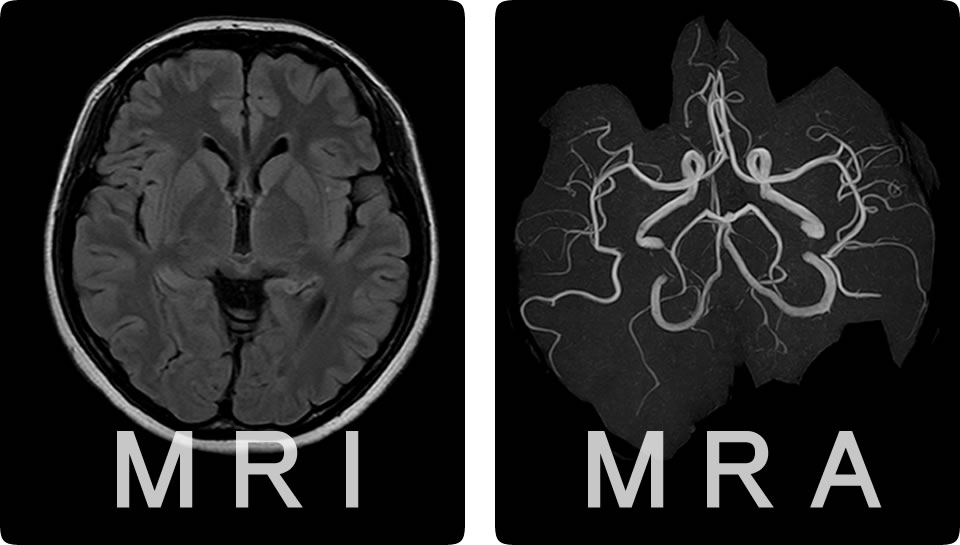

どんな検査をするの?

MRI検査・MRA検査

MRA検査は「脳の血管の細部まで」を視覚化して、

- 脳梗塞の原因になる「動脈の狭窄」

- クモ膜下出血の原因となる「未破裂脳動脈瘤」

などの早期診断が可能です。

どちらも放射線被曝のない安全な検査です。「頭が痛い」「めまいがする」などの症状があれば保険診療となります。まずは診察にお越しください。